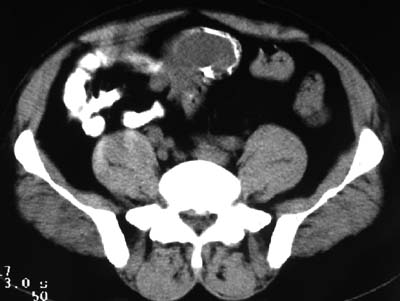

一、女,43岁,下腹部不适,子宫增大并可触及一硬物,活动度大。

典型的盆腔畸胎瘤。

病例1、盆腔畸胎瘤。病例2、盆腔占位压迫膀胱?还是膀胱占位?强化吧!

典型的盆腔畸胎瘤伴子宫肌瘤。

例1:畸胎瘤;

病理1.盆腔畸胎瘤和并子宫肌瘤

病例1、盆腔畸胎瘤,子宫体积增大,子宫肌瘤?病例2,囊腺瘤?

病例1,盆腔畸胎瘤并子宫肌瘤;病例2,囊性肿块,周围有壳状钙化,膀胱受压改变,考虑:脐尿管囊肿并感染,畸胎瘤?

考虑盆腔内畸胎瘤,子宫体积增大,建议增强扫描除外子宫病变